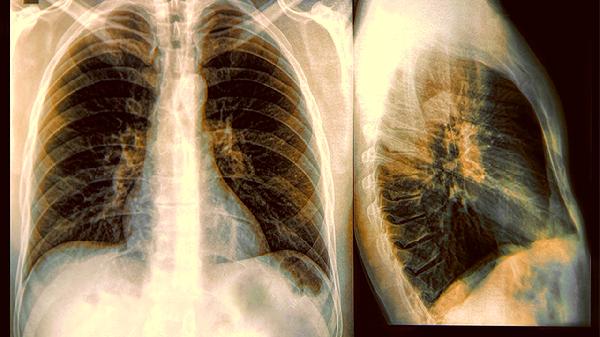

1、低剂量CT是金标准胸片就像用普通相机拍风景,而低剂量CT相当于高清单反,对5毫米以下的结节识别率能提高好几倍。虽然辐射量比胸片略高,但完全在安全范围内,相当于坐两次长途飞机的辐射量。